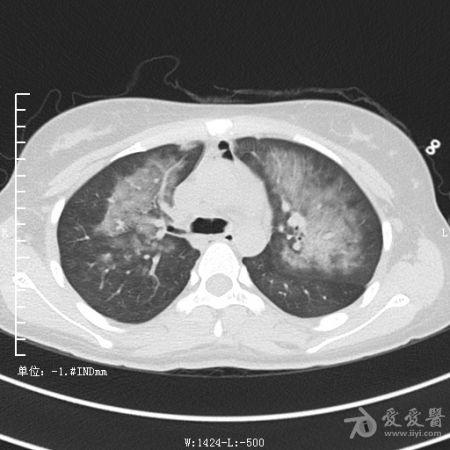

典型支气管扩张及肺水肿CT片

典型支气管扩张肺水肿